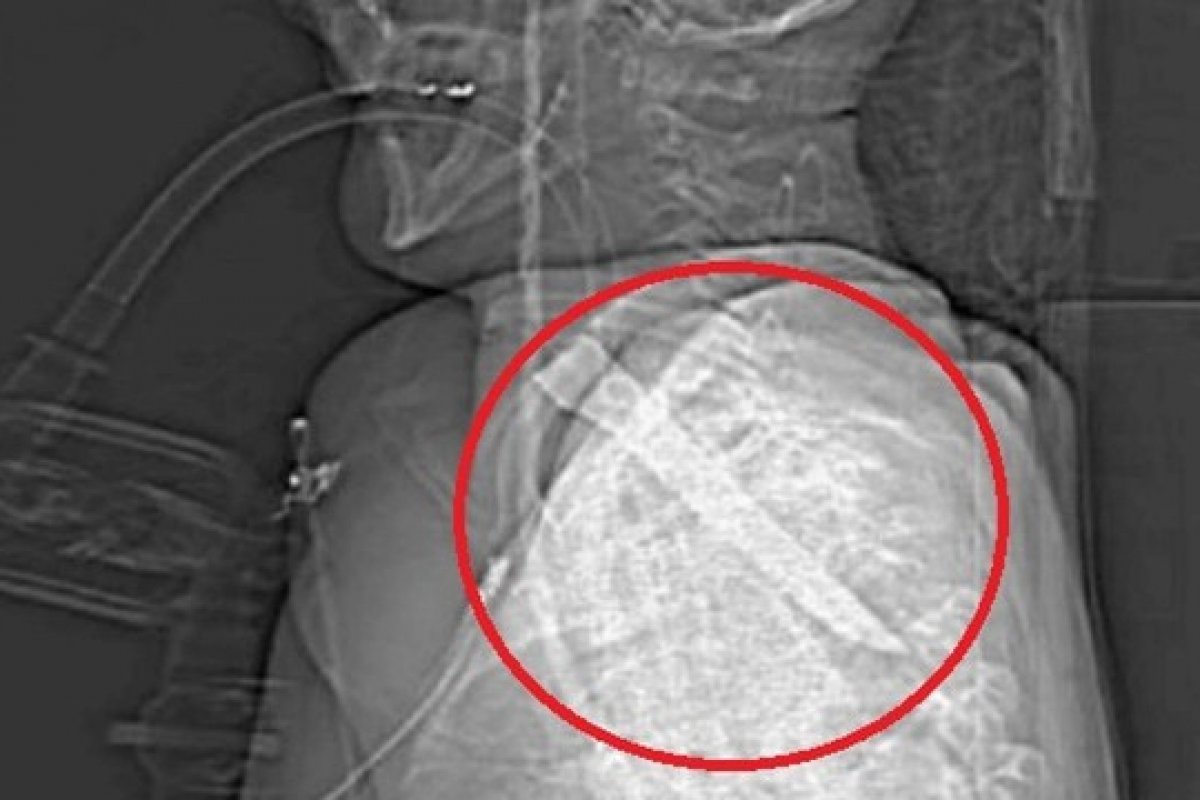

Um homem sobreviveu, após ficar com uma lâmina de 14 centímetros presa na garganta durante uma briga de bar em Shildon, na Inglaterra. A informação é do jornal britânico Daily Mail.

Vítima foi submetida a horas de cirurgia de emergência para remover a lâmina depois que ela o deixou a poucos milímetros da morte.

Durante o julgamento do agressor, Thomas Brazell, o juiz relatou que o cabo da faca quebrou e ficou preso dentro do pescoço da vítima. O objeto foi retirado durante cirurgia. O homem passa bem, mas não consegue mais mover o braço direito. Ele, que era jardineiro, não conseguiu retornar ao trabalho.